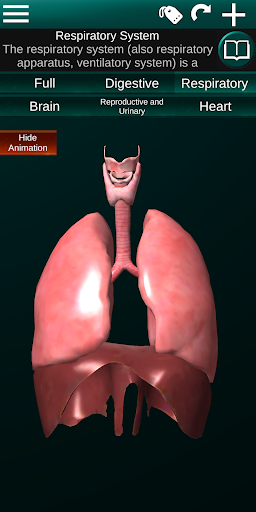

Показує 3D анатомічну модель основні органи людського тіла та опис кожного з них.

* Дихальна система, яка включає трахею, бронхи, легені та анімацію цієї системи.